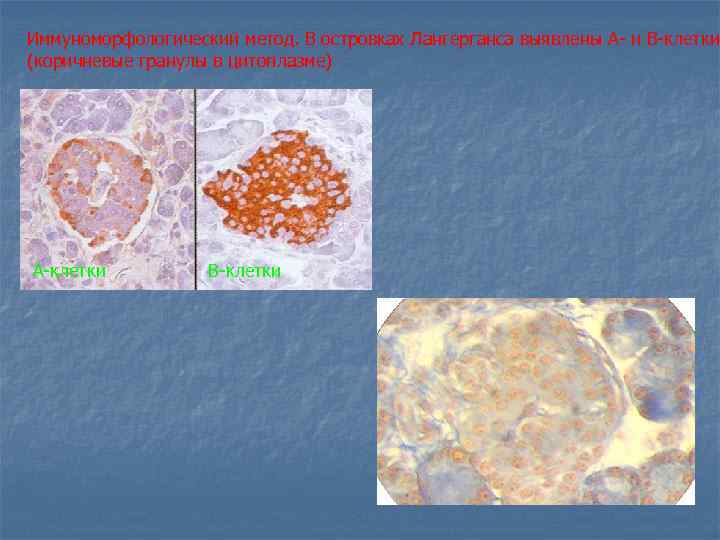

Иммуноморфологический метод. В островках Лангерганса выявлены А- и В-клетки (коричневые гранулы в цитоплазме) А-клетки В-клетки